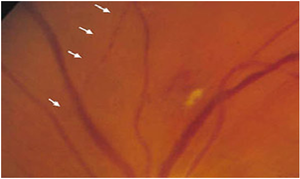

بفحص الأوعية الدموية الشبكية يظهر تدفق دموي قطاعي .

التشخيص السريري

التشخيص يتم بشكل فوري ومباشر سريريا عن طريق بداية مفاجئة لفقد القدرة البصرية الحاد و وجود ابيضاض في الشبكية . يوجد عيب ساحة بصرية موافق للمنطقة المتأذية . الأوعية الدموية المتأذية تظهر ركودة في التدفق الدموي (علامة التقطع Boxcarring ) وقد نجد آفة كاسرة للضوء ضمن الأوعية ( لويحات هولنهورست الكولسترولية Hollenhorst plaque ) , آفة بيضاء ضمن مقطع الوعاء الدموي وعادة في التفرع (صفيحات فيبرينية ) , أو لويحات كلسية كبيرة ( أمراض الصمامات القلبية ) . نلاحظ شرايين مستدقة . الأوردة قد تكون مستدقة أو متوسعة وقد تكون طبيعية ) .

- التصوير الوعائي بالفلوروسيئين يظهر تأخر في زمن امتلاء الشرايين الشبكية وتأخر في زمن العبور الشرياني الوريدي في المنطقة المتأذية . ركودة شديدة في الجريان الدموي للشرايين الشبكية . إن جريان الفلوروسيئين يبدي انتقالا بطيئا جدا الى الشبكية المحيطية على طول التفرعات الشريانية الشبكية . ومن النادر جدا ملاحظة غياب الامتلاء التام للأوعية الشبكية .